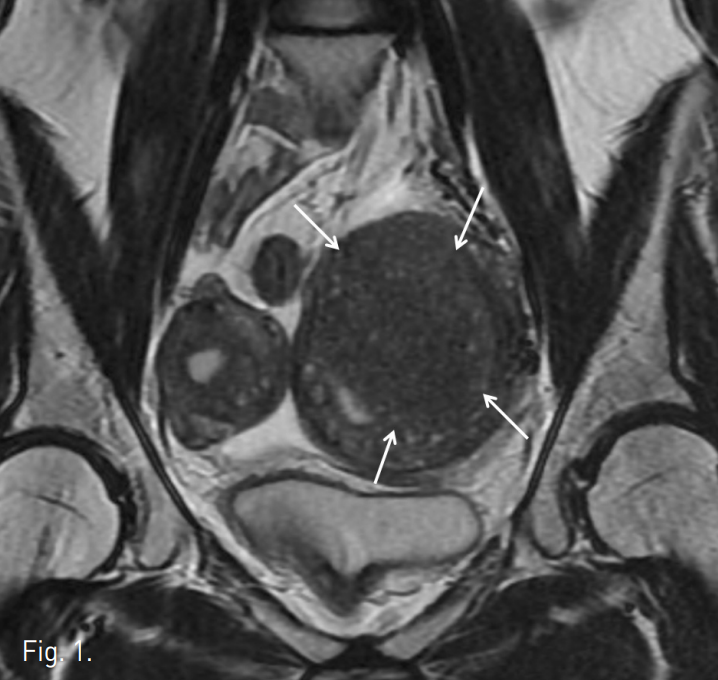

초음파 유도하에 우측 대퇴동맥을 천자하여 5F sheath(Terumo, Tokyo, Japan)를 삽입하였다. Pigtail 카테터(Cook, Bloonington, IN, USA)를 하부 대동맥에 위치시킨 후 골반조영술을 시행한 결과, 좌측 자궁동맥의 비대가 관찰되었다(Fig. 2a). 양측 자궁은 각각의 자궁 동맥으로부터 영양 공급을 받고 있었으며 두 동맥은 거의 서로 연결되어 있지 않았고 완전히 독림된 자궁이 조영되었다(Fig. 2b). 5 F Cobra 카테터(Cook, Bloonington, IN, USA)로 좌측 내장골동맥에 진입시키고 Microferret 카테터(Cook, Bloonington, IN, USA)로 좌측 자궁동맥을 선택하였다. 자궁동맥의 상행분절에 Microferret 카테터를 위치시키고 polyvinyl alcohol(PVA)(Contour, Bostonscientific, Fremint. Calif)을 이용하여 자궁동맥 색전술을 시행하였다. 150-250 micrometer, 250-355 micrometer, 355-500 micrometer의 PVA를 순서대로 사용하는 1-2-3 프로토콜로 색전술을 시행하였다. 이때 조영제와 식염수가 1:1로 섞인 용액에 PVA입자를 넣어서 총 60ml를 만들었는데, 각각의 사용한 양은 20cc( 1/3 vial), 40cc(2/3 vial), 20cc(1/3 vial) 이었다. 10 번의 심장박동 동안 자궁 동맥내에 조영제의 정체가 보일 때까지 색전술을 시행하였다. 우측 자궁동맥 조영술에서 좌측 자궁과 연결 되는 작은혈관이 관찰 되었으나 향후 체외수정을 고려하여 색전술을 시행하지 않았다(Fig. 3). 색전술 후 3개월째 시행한 MR에서 선근증 완전괴사를 관찰할 수 있었으며 좌측 자궁은 44.3%의 볼륨감소를 보였다(Fig. 4a-b). 시

Fig. 3

The right uterine arteriogram demonstrates small branch (arrows) outside the right-sided uterus communicating with the left-sided uterus.